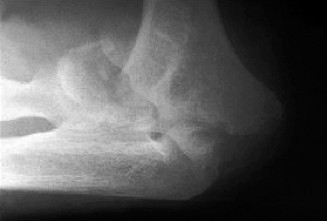

Understand common complications associated with performing surgery for scapulothoracic bursitis? CASE 33 A 42-year-old female presents to the office for follow up after sustaining a minimally displaced radial head fracture 3 months prior. She states she was initially treated in long-arm splint by the ER and did not follow up with an orthopaedic surgeon until now. Per her report, she removed the splint 4 weeks after the injury, but did not move her elbow due to pain. She now has no pain but is unable to reach that hand to her face or head. The remaining history is significant for previous ulnar nerve surgery for which she is unable to provide details. On physical examination, her upper extremity is normal except for limited flexion/extension, measured to be 80 to 50 degrees by goniometer. In addition, she has a well-healed surgical incision about the medial elbow, consistent with a previous surgery on her ulnar nerve. Her images are shown (Figs. 2–82 to 2–84).

Figure 2–82